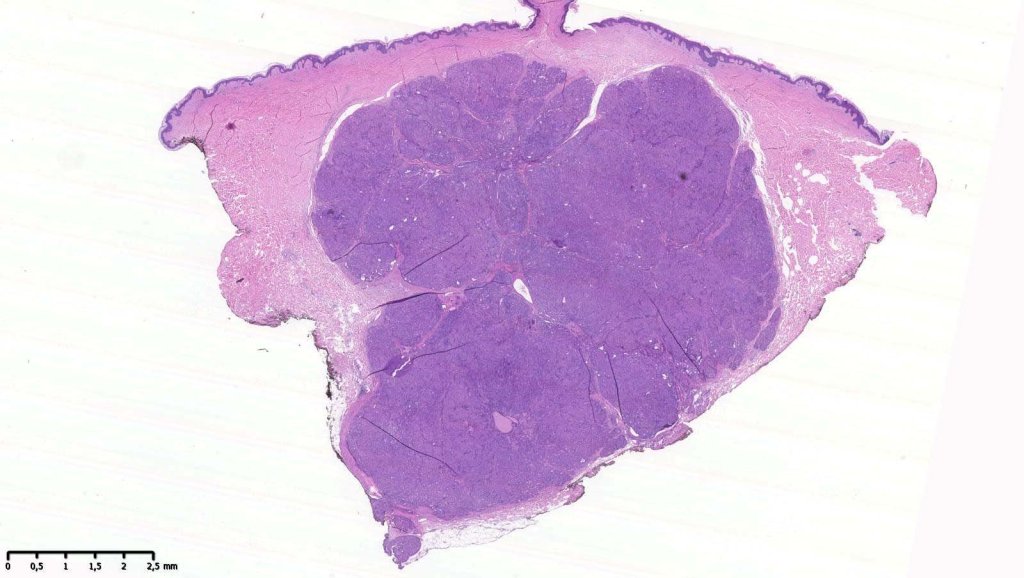

Histological features

•Solid or cystic sharply defined nodule in dermis sometimes extending into subcutaneous fat

•Eccrine (predominantly poroid & cuticular cells) & apocrine variants (association with a follicle, decapitation secretion & GCDFP-15+ve)